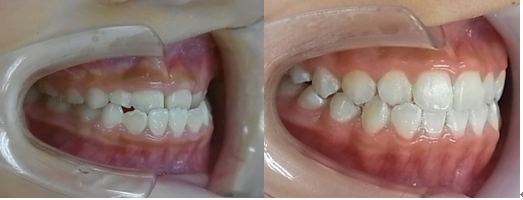

その後、矯正装置を除去していきます。

治療前はAngleⅢ級でしたが歯(第一小臼歯)を抜く事無くAngleⅠ級に改善しています。つまり、矯正治療の最終目標である個性正常咬合になっています。

治療前 治療後